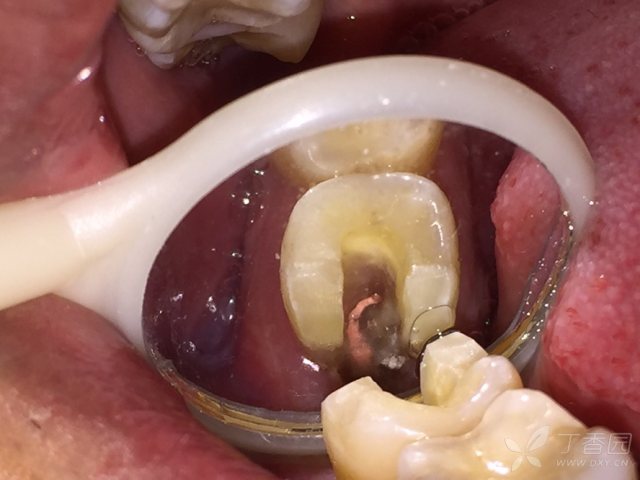

![下7c型根管一例 [病例帖]](https://img1.dxycdn.com/2017/1107/709/3242847479835208464-16w.jpg!w640)

下7c型根管一例 [病例帖]

640x480 - 40KB - JPEG